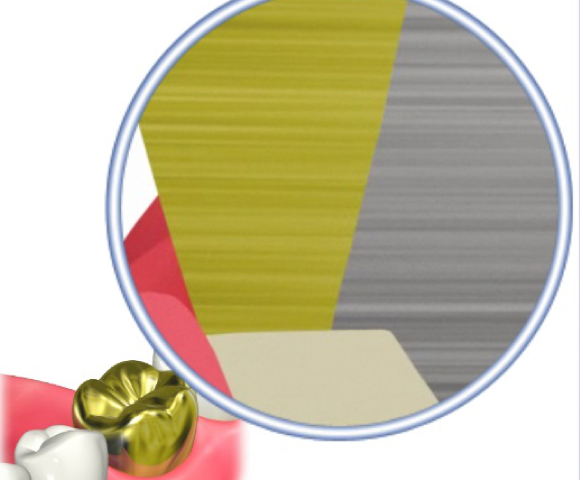

■歯磨きではとれない歯石や合っていない汚れが貯まりやすい被せ物の除去をします。

合っていない冠の除去し仮の歯に

治療前(症例)

治療後(症例)

歯周病治療後被せ物をしっかりフィットさせることで歯周病の再発を防ぎます。

治療前(症例)

治療後(症例)

治療前、被せ物と冠の間に段差がありフィットしていませんが、歯周病治療後しっかりと被せ物をフィットできています。